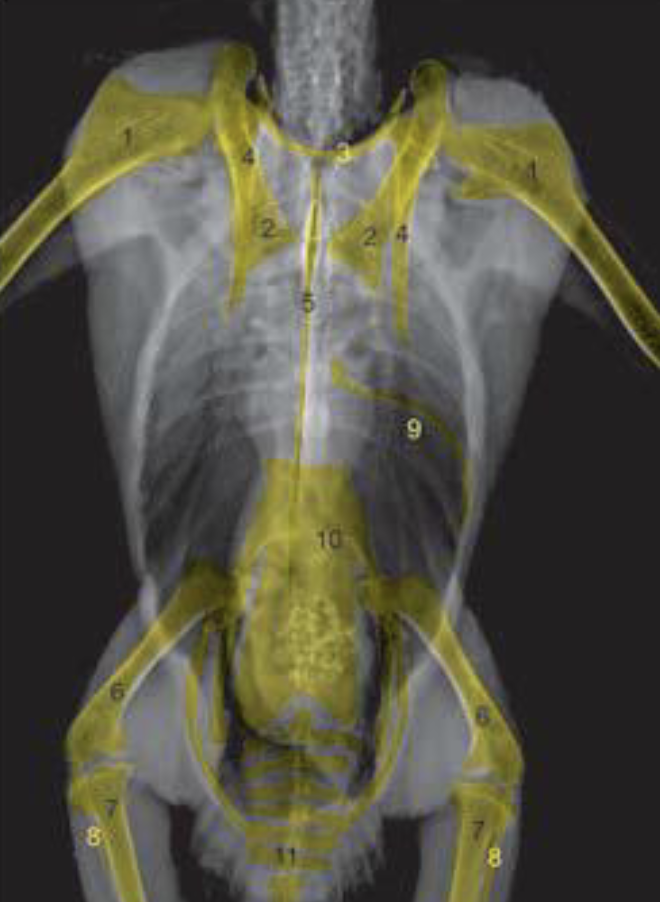

What are the anatomical structures labelled in this image?

A

7: tibiotarsus

1: humerus

3: clavicle

2: coracoid

11: pygostyle

6: femur

4: scapula

8: fibula